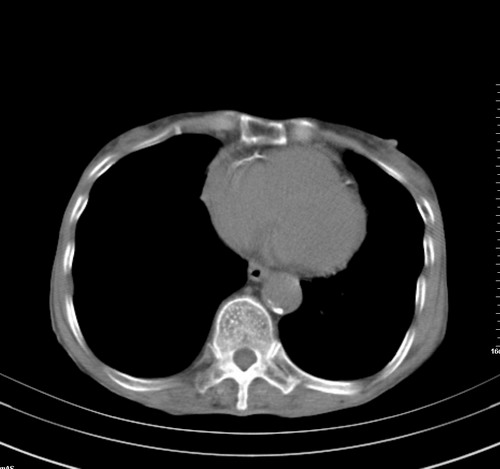

中后纵隔占位,气管、食道受压、变形、移位。恶性可能性大。

考虑:中后纵隔转移瘤可能性大,主动脉硬化。

中后纵隔占位, 考虑:转移瘤不除外.

纵隔淋巴结肿大,考虑转移而来

中后纵隔转移瘤可能性大,主动脉硬化。

后中纵隔团块影,伴气管、食道受压移位,首先考虑转移瘤,肝s5段低密度灶。建议增强检查,另外其结肠是否有问题请提供,右肺部分肺叶局限含气增多,考虑局限肺气肿。

建议强化检查,考虑纵隔型肺癌,小细胞可能性大。

后中纵隔团块影,伴气管、食道受压移位,首先考虑转移瘤,肝表现同11773。

后中纵隔淋巴结肿大,首先考虑转移瘤。